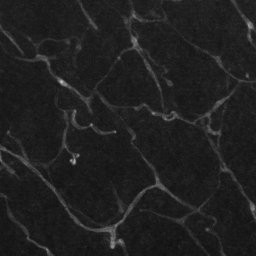

Semantic segmentation of blood vessels is an important task in medical image analysis, but its progress is often hindered by the scarcity of large annotated datasets and the poor generalization of models across different imaging modalities. A key aspect is the tendency of Convolutional Neural Networks (CNNs) to learn texture-based features, which limits their performance when applied to new domains with different visual characteristics. We hypothesize that leveraging geometric priors of vessel shapes, such as their tubular and branching nature, can lead to more robust and data-efficient models. To investigate this, we introduce VessShape, a methodology for generating large-scale 2D synthetic datasets designed to instill a shape bias in segmentation models. VessShape images contain procedurally generated tubular geometries combined with a wide variety of foreground and background textures, encouraging models to learn shape cues rather than textures. We demonstrate that a model pre-trained on VessShape images achieves strong few-shot segmentation performance on two real-world datasets from different domains, requiring only four to ten samples for fine-tuning. Furthermore, the model exhibits notable zero-shot capabilities, effectively segmenting vessels in unseen domains without any target-specific training. Our results indicate that pre-training with a strong shape bias can be an effective strategy to overcome data scarcity and improve model generalization in blood vessel segmentation.